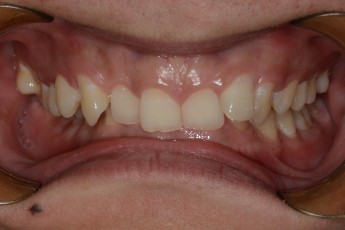

BEFORE & AFTER

- 덧니교정